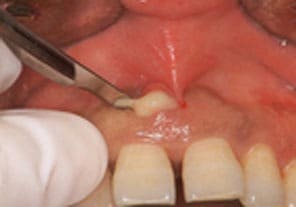

膿の部分を切開、洗浄をし、薬を服用して症状を落ち着かせます。その後根本的な治療をおこないます。